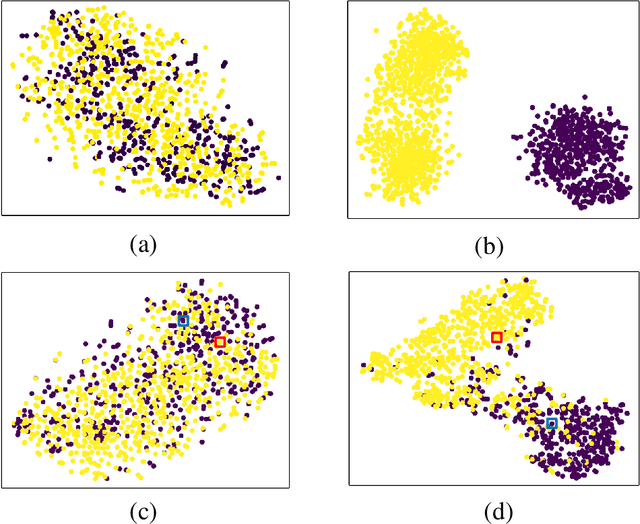

Recently, the outbreak of Coronavirus Disease 2019 (COVID-19) has spread rapidly across the world. Due to the large number of affected patients and heavy labor for doctors, computer-aided diagnosis with machine learning algorithm is urgently needed, and could largely reduce the efforts of clinicians and accelerate the diagnosis process. Chest computed tomography (CT) has been recognized as an informative tool for diagnosis of the disease. In this study, we propose to conduct the diagnosis of COVID-19 with a series of features extracted from CT images. To fully explore multiple features describing CT images from different views, a unified latent representation is learned which can completely encode information from different aspects of features and is endowed with promising class structure for separability. Specifically, the completeness is guaranteed with a group of backward neural networks (each for one type of features), while by using class labels the representation is enforced to be compact within COVID-19/community-acquired pneumonia (CAP) and also a large margin is guaranteed between different types of pneumonia. In this way, our model can well avoid overfitting compared to the case of directly projecting highdimensional features into classes. Extensive experimental results show that the proposed method outperforms all comparison methods, and rather stable performances are observed when varying the numbers of training data.